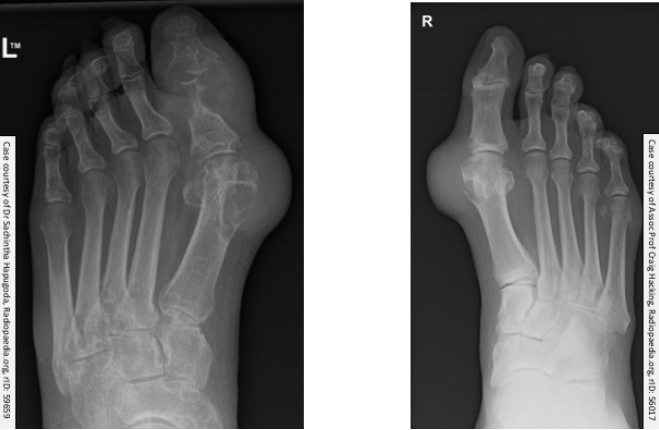

The abnormalities in these X-rays are typical of which condition?

Gout